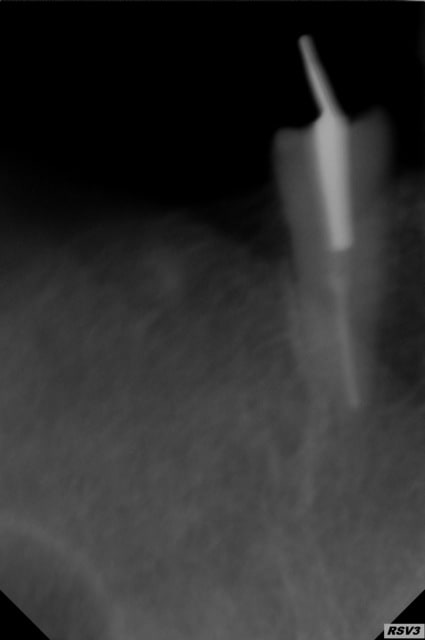

Z'avais pas vu l'edit et les radios.....

Mouais c'est pas génial, non?

T'as trop taillé ce qui sort de la racine et du coup ça me parait un peu ledge pour se cramponner dessus.

Quid de l'image en distal de la dent perceptible sur le premier cliché??? Carie, poche paro????

Moi je virerais ce truc mais pour la suite je sais pas si j'opterais pour bridger les dents et faire des attachements car risque que ça se casse la gueule un de ces 4.... 6 chances qu'un des piliers foire

Faudrait voir l'oclusion, si elle serre, si y'a la place, l'état des autres racines.